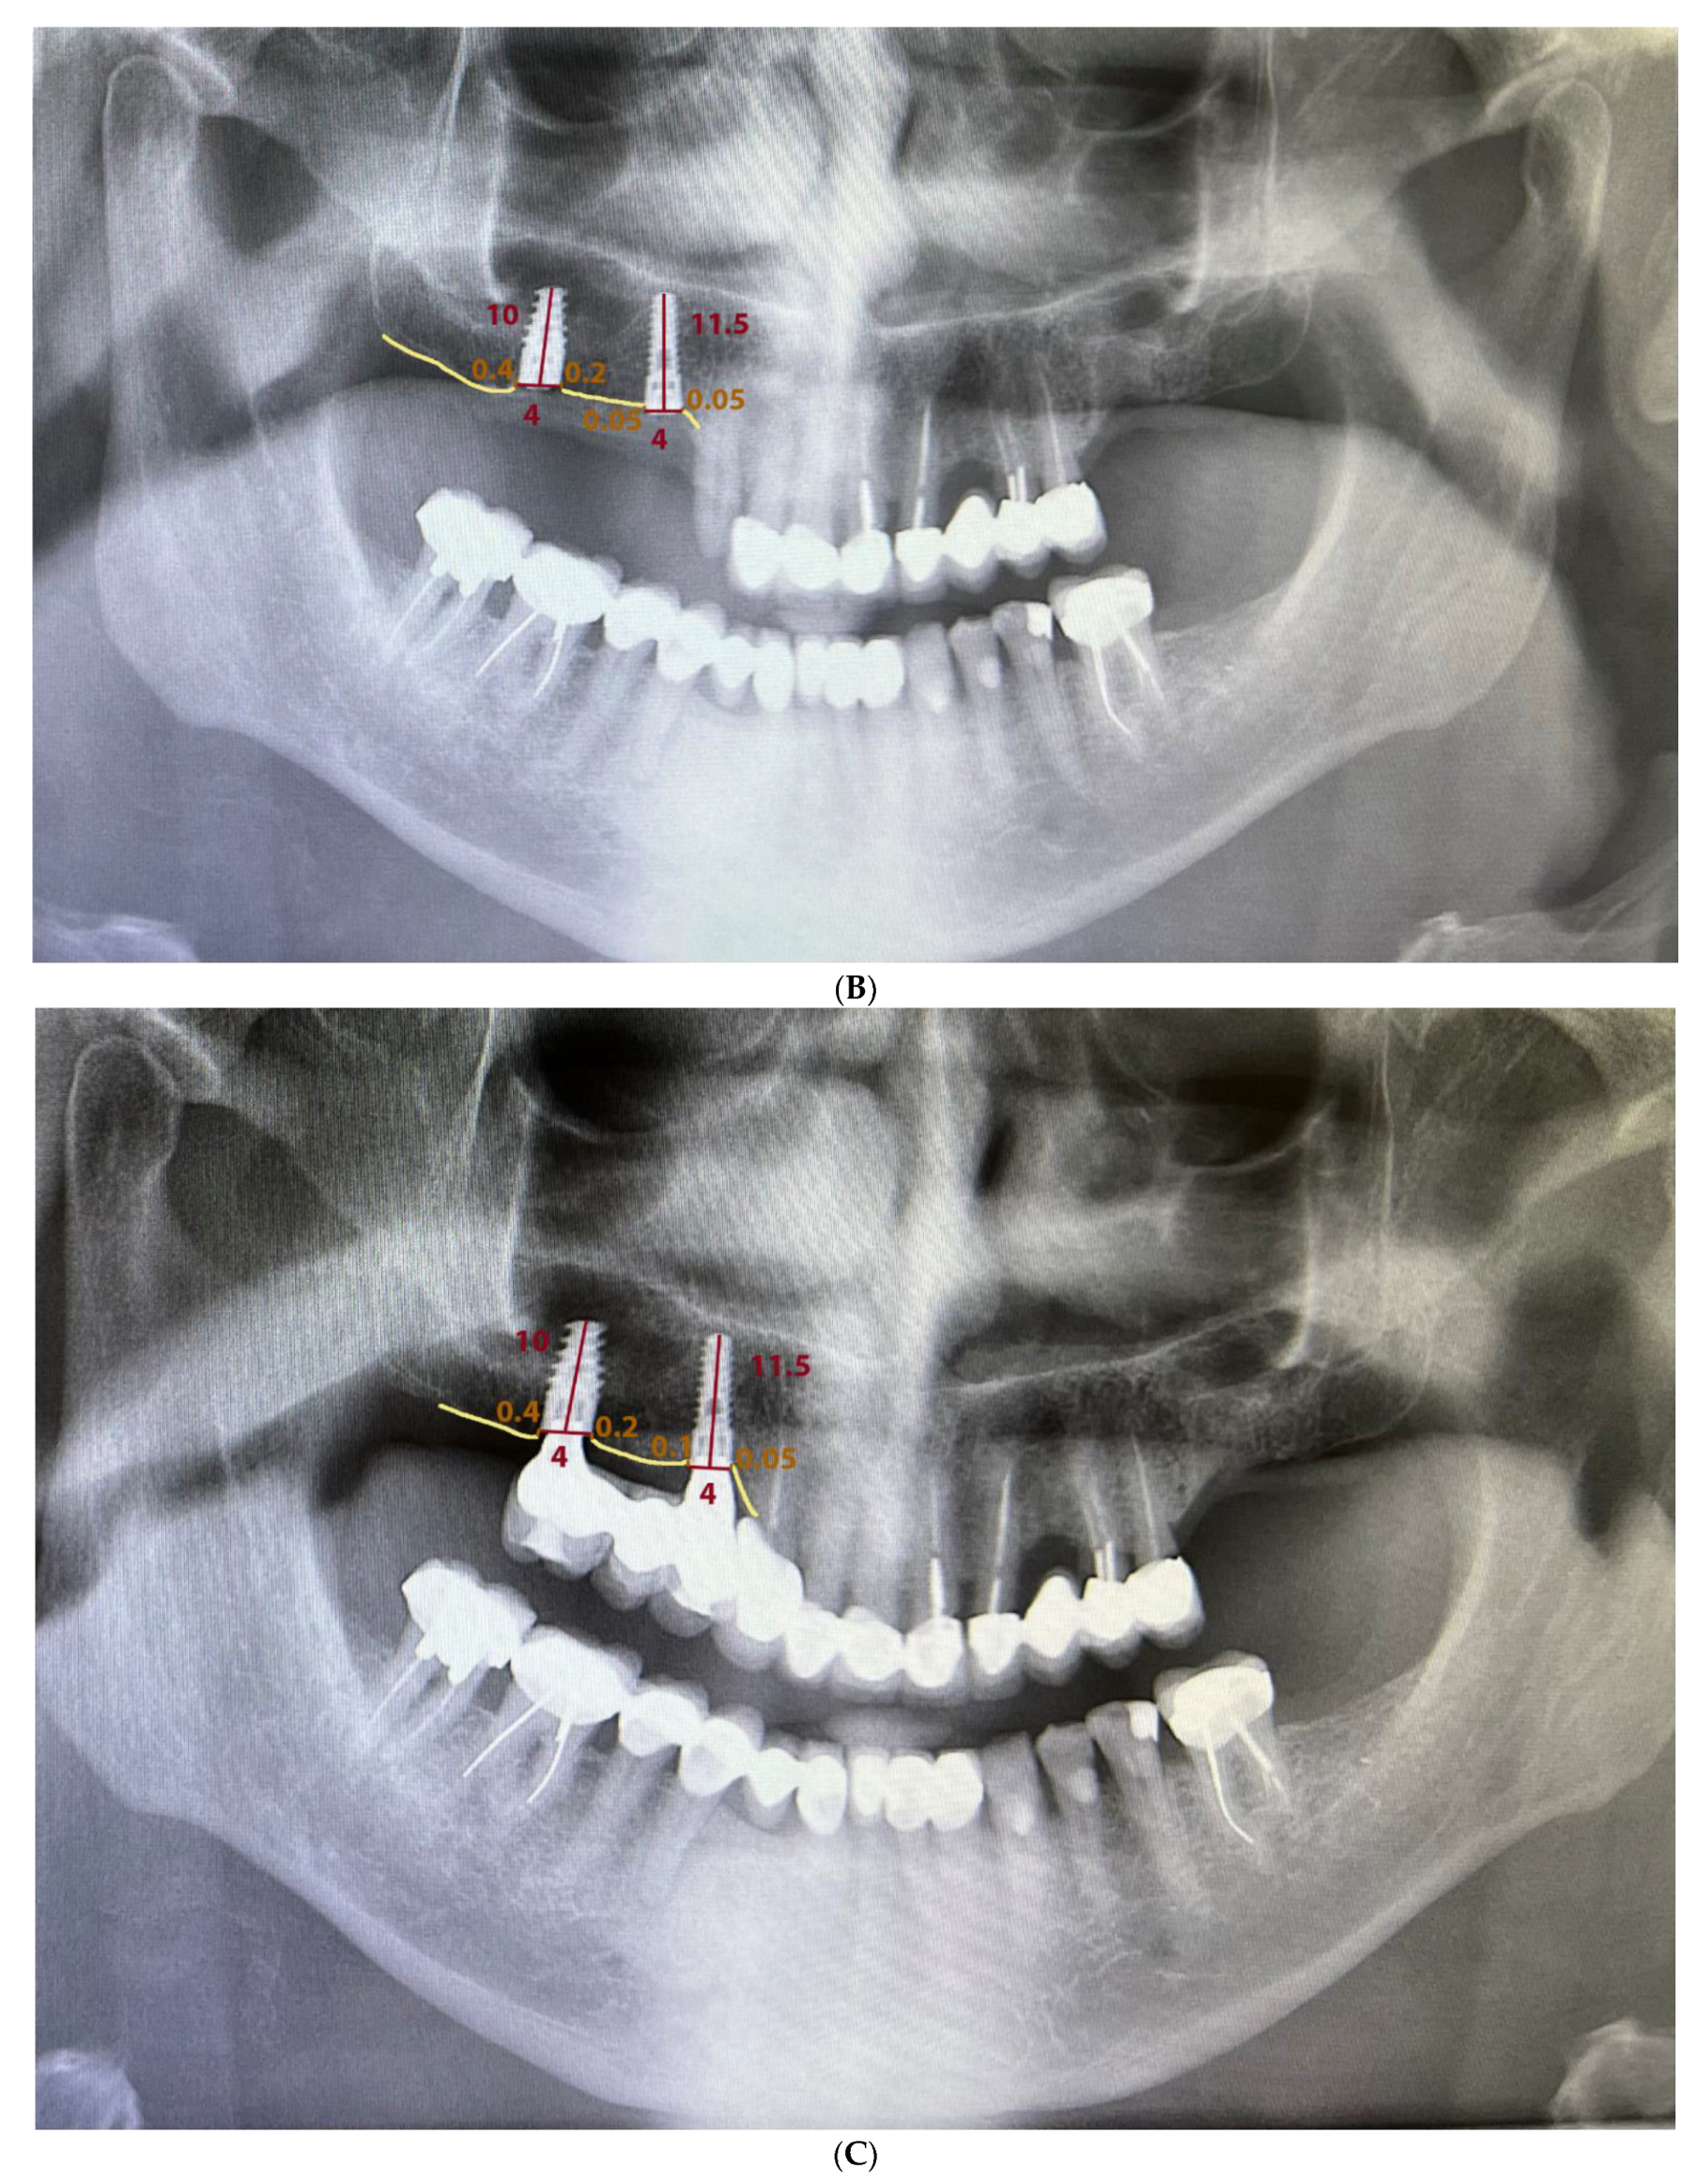

Measurements were made by using Planmeca Romexis® software to process 2D images generated by the X-ray units. The calibration tool ensured that the measurement was correctly performed, given that it takes into account the length of each implant. Since all patients were required to have a CBCT before surgery, it was decided not to perform cone-beam radiographs to limit multiple radiation exposures. To carry out the measurements, two points were marked on the implant platform that, when joined horizontally, represented zero height. Perpendicular to this line, two straight lines were drawn mesial and distal to the implant until contact with the bone. If the implant was coronal to the bone, the result would be interpreted as negative, whereas, if the implant was infracrestal, the result would be positive. The difference between the mean of the mesial and distal measurements at different times was used to calculate the bone loss in the orthopantomography (Figure 2).

Figure 2. Measurement of peri-implant bone loss: (A) after implant placement, (B) after 1 month, and (C) after 4 months.